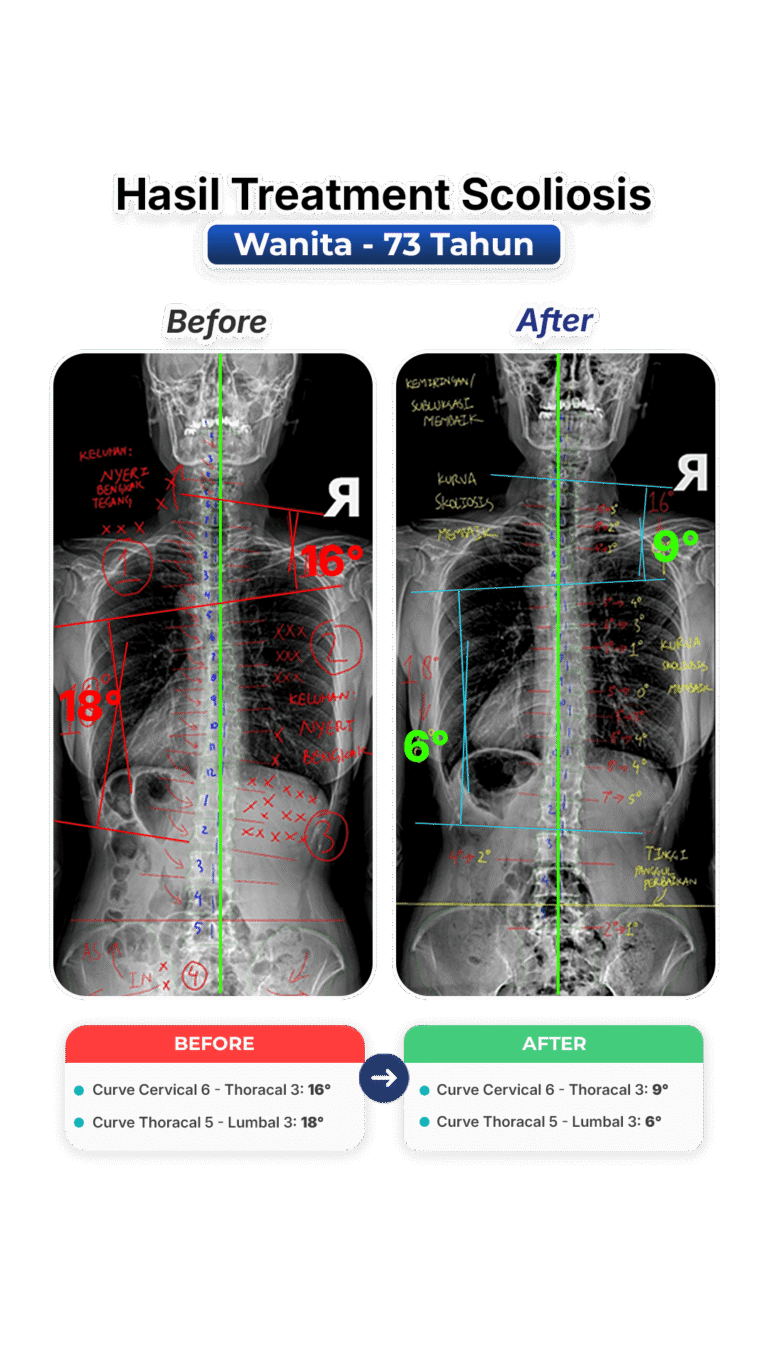

Perubahan nyata setelah mengikuti program terapi skoliosis di VLife Medical Galaxy Mall 3.

Perawatan scoliosis dilakukan melalui evaluasi tulang belakang menyeluruh, program terapi bertahap, fokus keseimbangan postur, mengurangi nyeri, memperlambat progres kelengkungan, serta meningkatkan fungsi gerak harian pasien secara aman dan terkontrol medis.

Penanganan skoliosis berbasis evaluasi postur menyeluruh, terapi manual khusus, latihan koreksi, serta pemantauan progres di setiap sesi. Dibuat untuk remaja dan dewasa yang ingin mengendalikan kelengkungan skoliosis dan mengurangi nyeri.